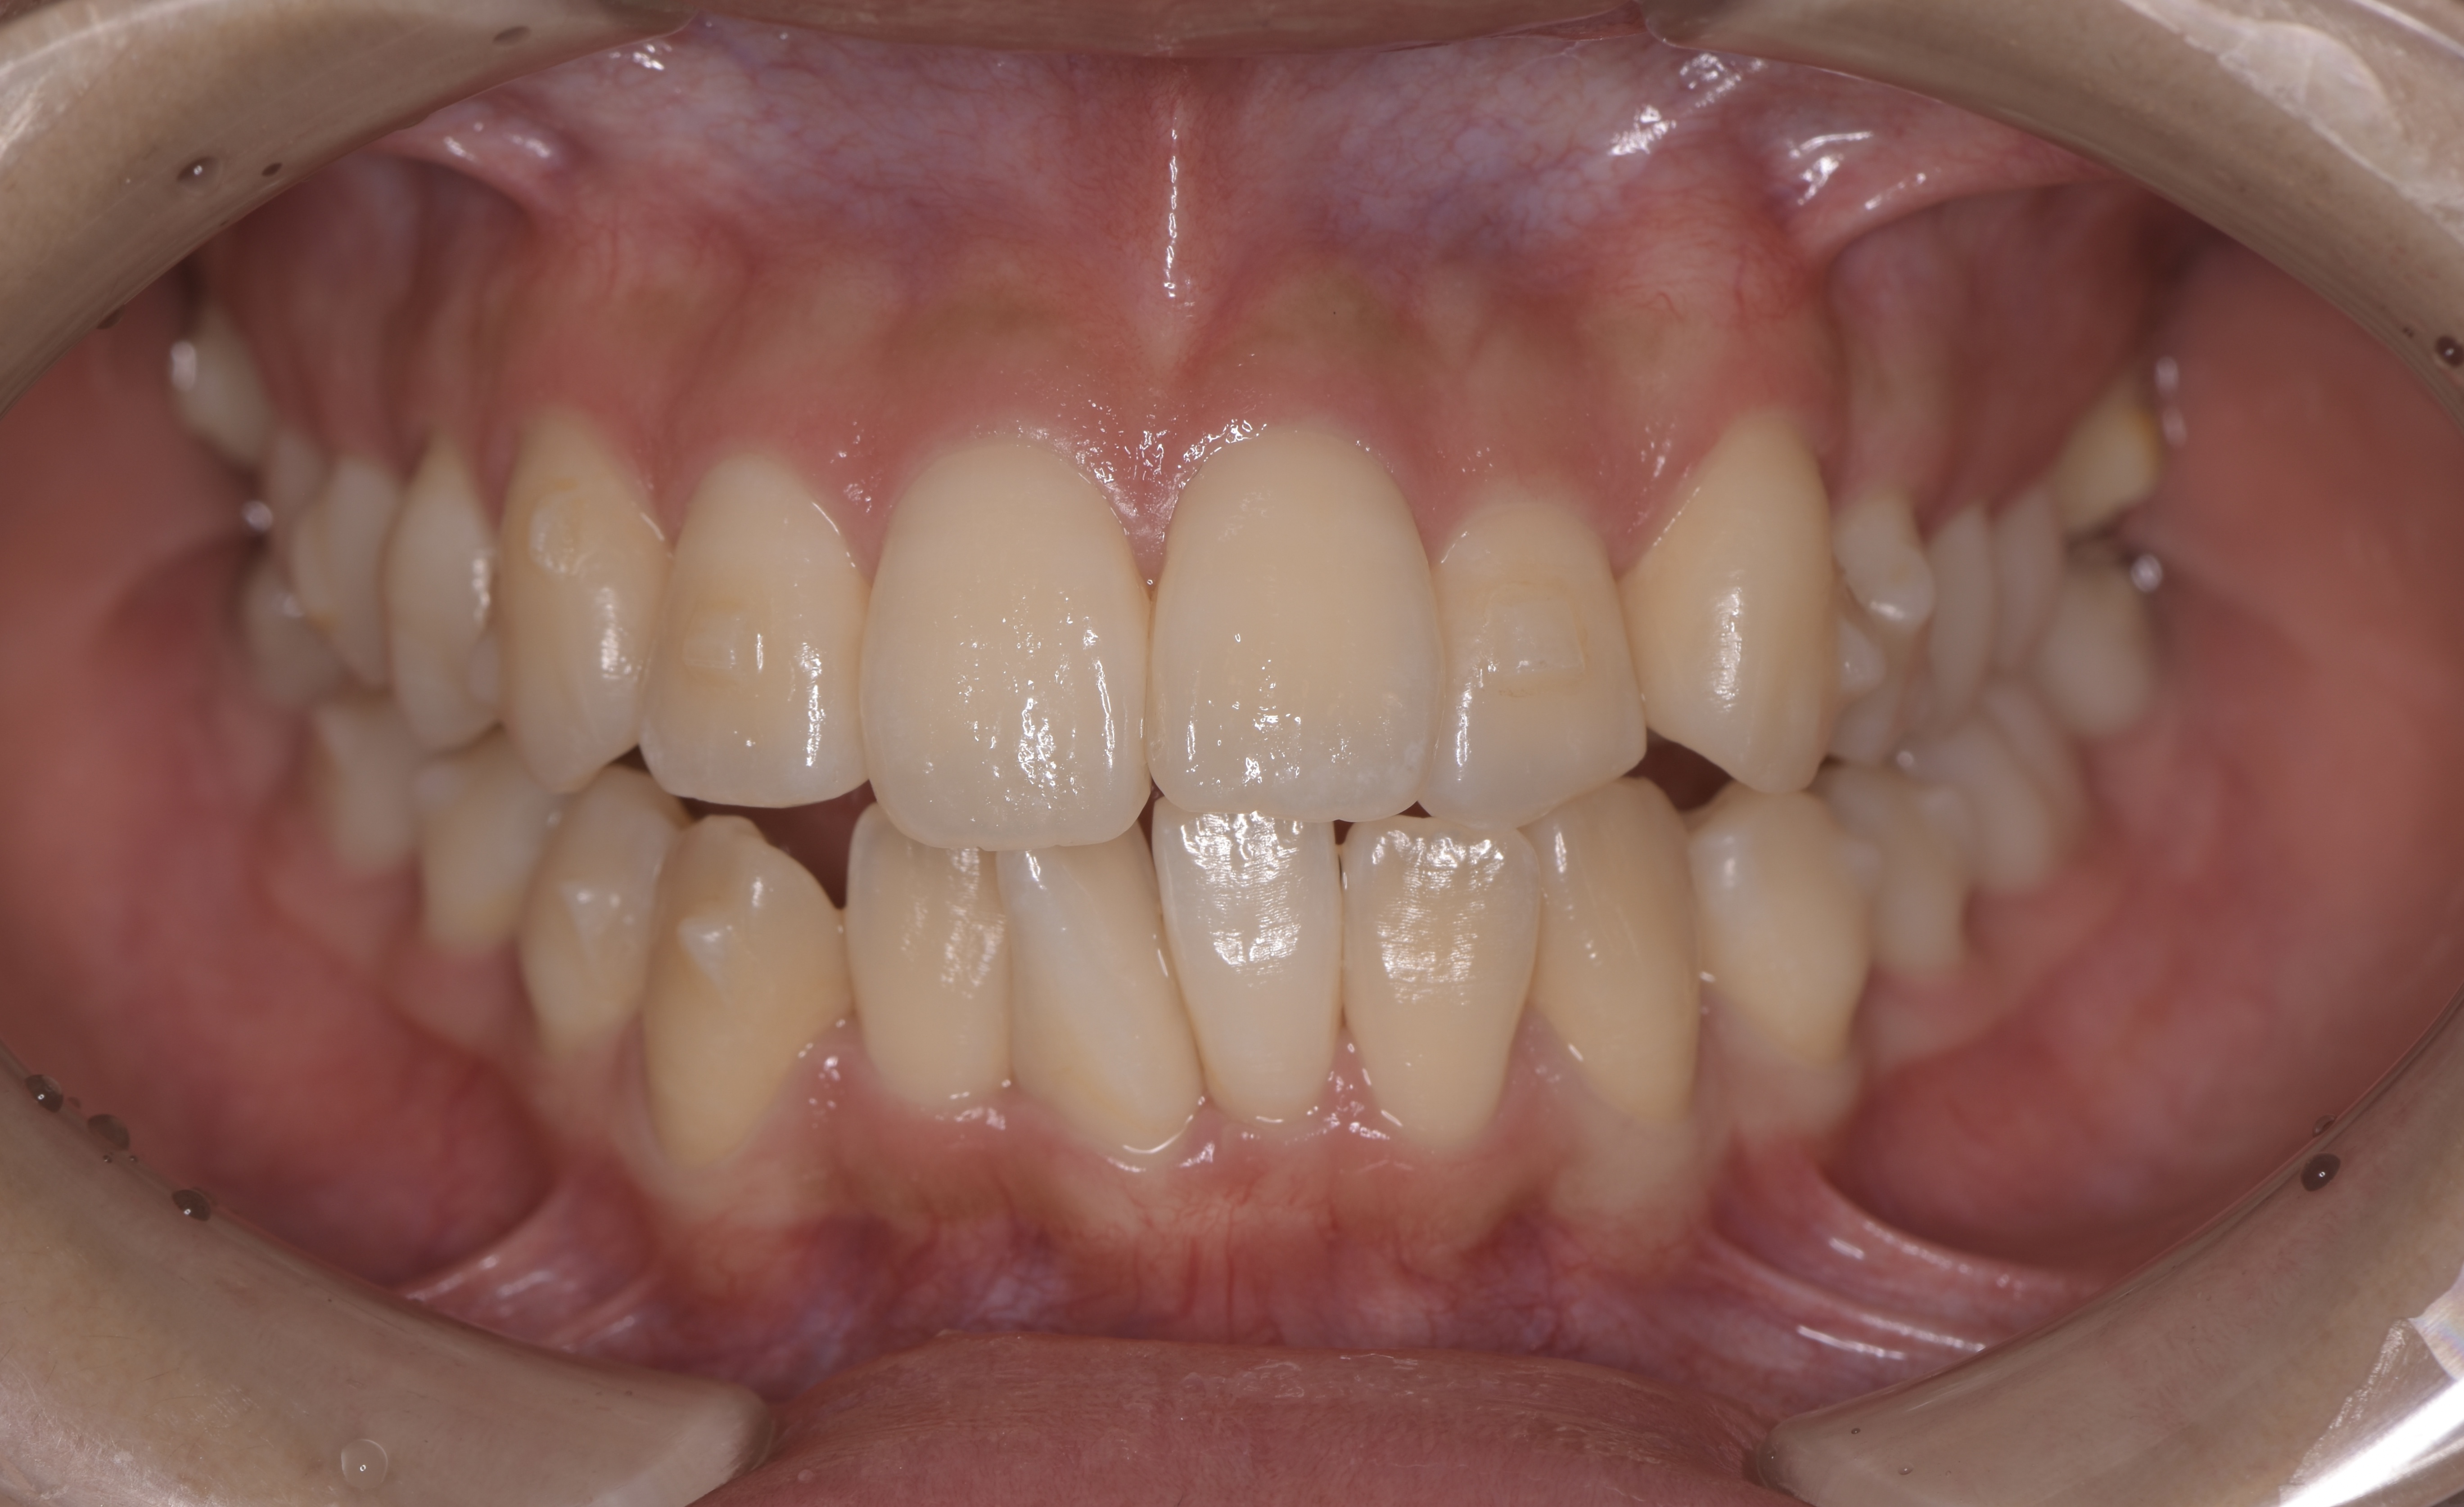

顎に歯が並ぶスペースが足りないことによって、特に上顎左2番の低位口蓋側転位と、下顎左1番の捻転が目立ちます。これにより前歯部叢生を伴った上顎前突と言われる状態で、不正咬合による顎関節への負担が主訴となっている顎の痛みに繋がっているものと考えられます。ただし目立つ虫歯(カリエス)もなく、健康な歯と歯ぐきを保ってらっしゃるデンタルIQの高い患者さんということがわかります。

約3年の動的期間が経過しました。ご覧のように上顎は理想的な歯列弓に沿って歯が並んでいます。大きく舌側に傾斜していた上顎左2番の低位口蓋側転位も正しい位置に排列しています。下顎も治療計画通りに進み、左下1番の捻転も移動が進んでいることがわかります。この後マウスピースの装着を続けて頂き、治療期間の終了後に約6ヶ月の保定期間となります。これは矯正治療で骨が再生(添加)された部分を安定させて後戻りをさせないために必要な期間です。